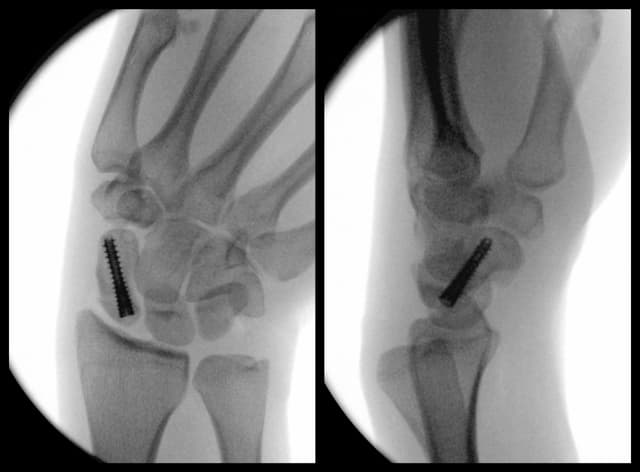

Scaphoid Fracture Fixation

Pre-op

Post-op